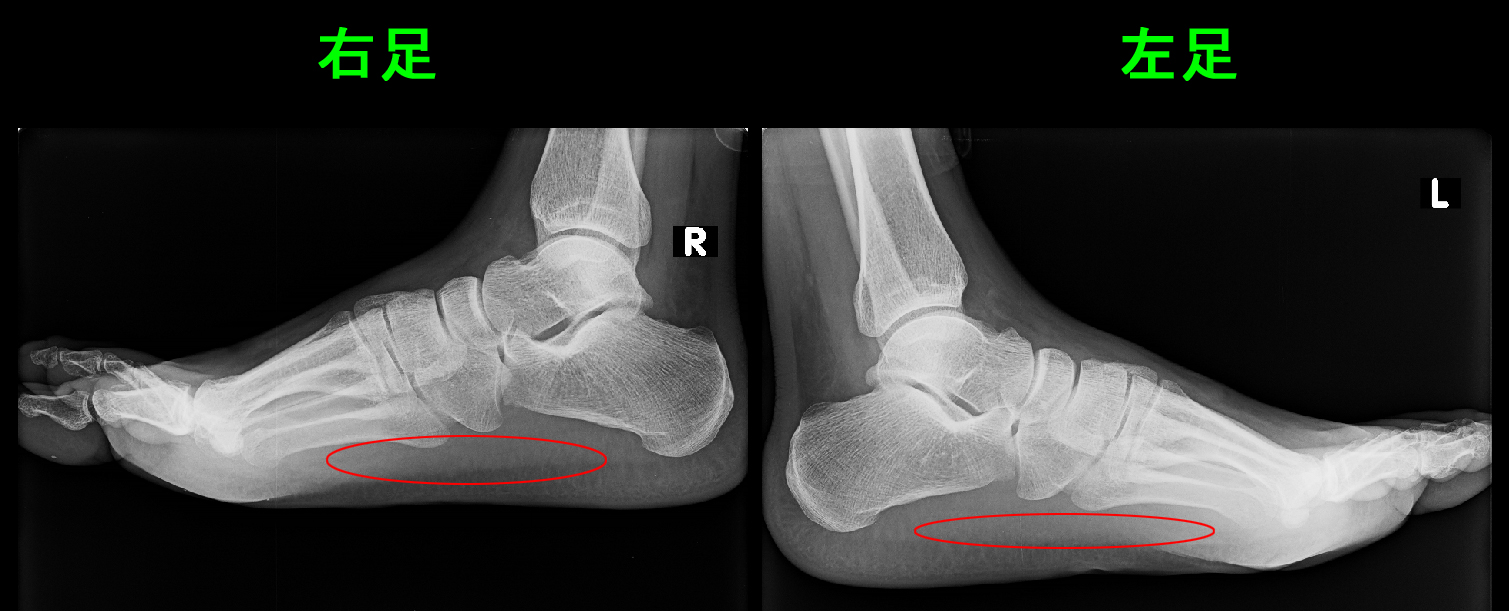

31才男 初診時Xp.jpg

赤丸部分が痛みの領域です。前足部が痛くないのでかかとを浮かして前足部で歩くためにおばあさんのような姿勢となっていたと思われます。